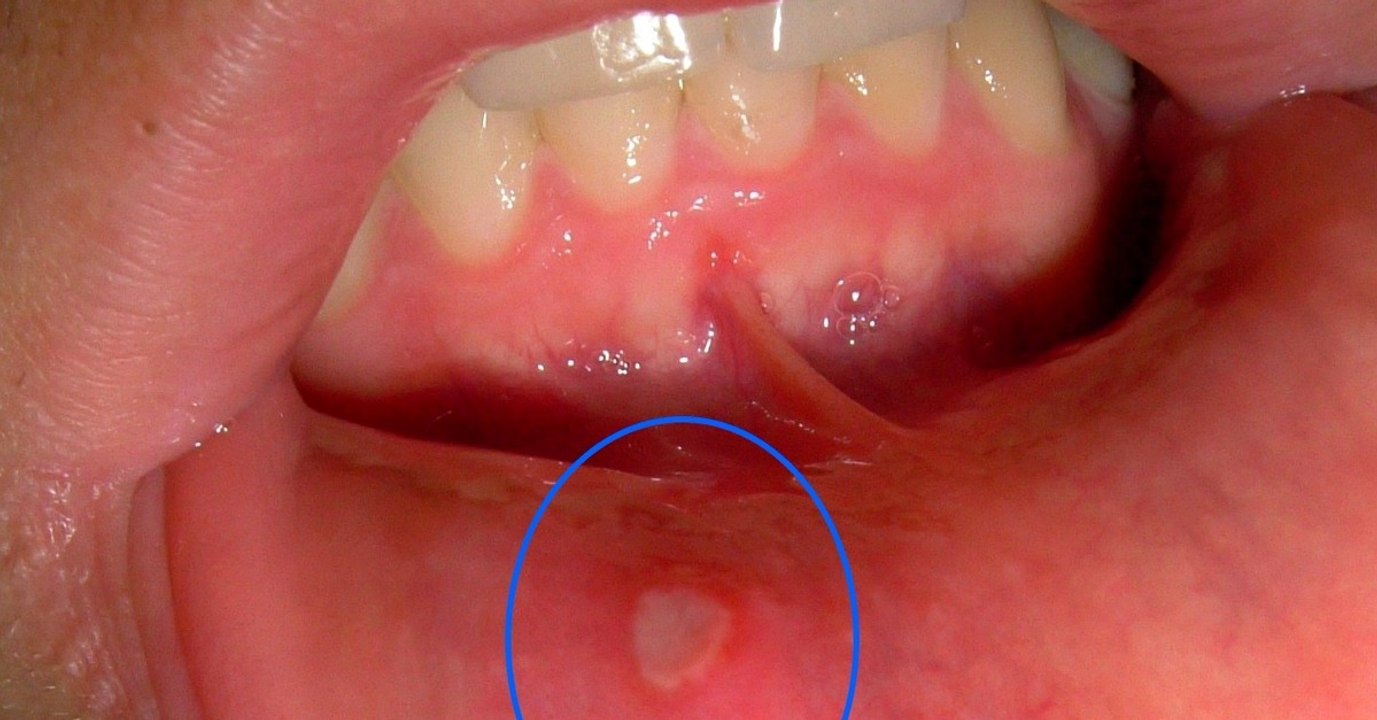

Aphten im Mund: Schmerz lindern und Heilung befördern mit diesen Lebensmitteln 0:47

Aphten im Mund: Schmerz lindern und Heilung befördern m...

OhMyMag DE 9 views